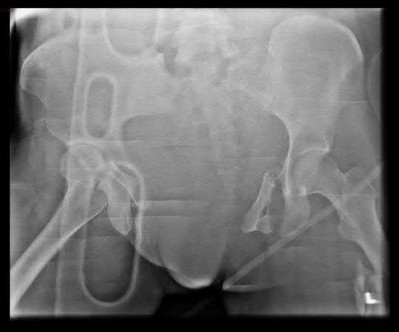

A 35 year-old female presents after prolonged extrication from a motor vehicle collision complaining of severe pelvic pain. Physical examination reveals diminished perianal sensation. She is otherwise neurologically intact. Figures A through D are radiographs and representative CT cuts of her injury. Which of the following nerve roots has likely been injured by the acute trauma?

The clinical scenario is consistent with a high-energy sacral fracture. The radiographs in figures A and B demonstrate a sacral fracture with posterior displacement of the right hemipelvis seen on the inlet view. Figures C and D are axial and sagittal CT images which show a displaced fracture of the right

hemisacrum along with a transvere fracture component through the S3 body . Diminished perianal sensation is concerning for an S2 nerve root injury.

Mehta et al reviewed the current management of sacral fractures. They note that the S1 and S2 nerve roots are more likely to be injured with sacral fractures as they occupy 1/3 to 1/4 of the neural foramina, as opposed to S3 and S4, which only occupy 1/6 of the neural foramina.

Robles reviewed the current literature to ascertain principles of evaluation and treatment for transverse sacral fractures. The author notes that injury to nerve roots S2 to S5 is manifested by impairment of urinary and anal continence and sexual function.

The first illustration demonstrates the sacral nerve root dermatomal distribution. The second shows a pelvic cadaver dissection demonstrating the sacral nerve roots as they exit the foramina.